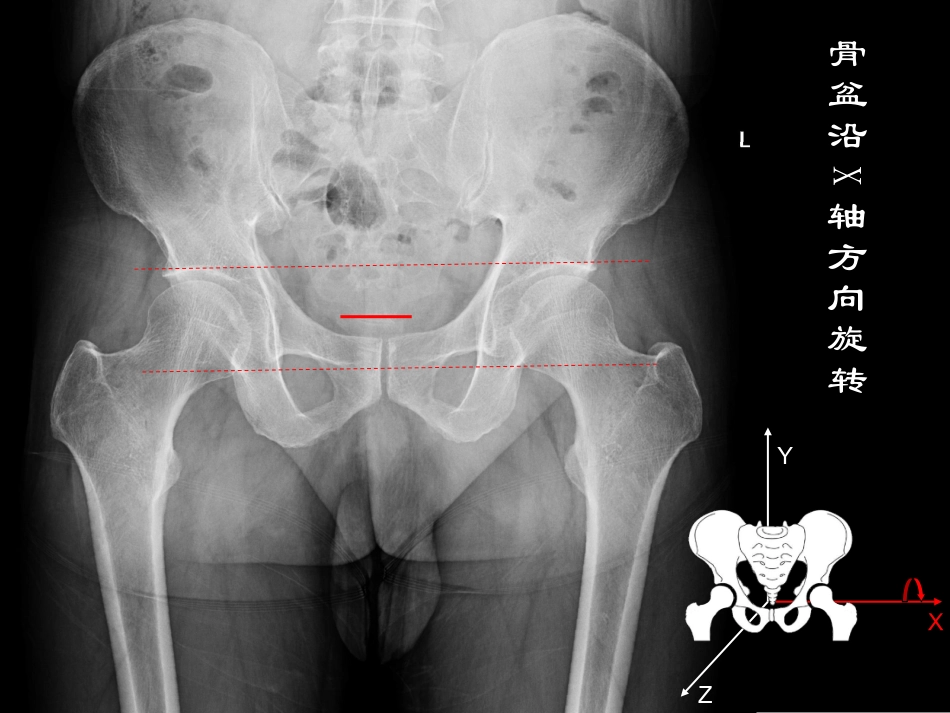

成人发育性髋关节发育不良影像学表现如何判断一张X线片的好坏XYZ骨盆沿X轴方向旋转XYZXYZ骨盆沿X轴方向旋转骨盆沿Y轴方向旋转XYZ骨盆沿X轴方向旋转骨盆沿Z轴方向旋转髋关节常用指标的测量•沈通线与髂颈线•外侧CE角•臼顶倾斜角•髋臼覆盖率•颈干角•夏普角•前CE角•股骨颈前倾角沈通线髂颈线Shenton线:又称耻颈线,为股骨颈内缘与闭孔上缘之间的连线,正常为连续的弧形,如不连续说明髋关节有不同程度的半脱位。Calve线:又称髂颈线,为髂骨外缘与股骨颈外缘光滑的弧线,如不连续说明髋关节有不同程度的半脱位。外侧CE角正常>25°Wiberg外侧CE角:异常的外侧CE角是诊断髋关节发育不良的标准之一,用来评估骨性髋臼在股骨头上方及外侧的覆盖,正常值均大于25°,20~25°为临界值,小于20°则可诊断为髋关节发育外侧CE角发育不良<20°臼顶倾斜角正常<10°被用来评价冠状位上髋臼顶的方向,以及股骨头外上方的覆盖,髋臼的关节承重面在X线片上表现为外形类似“眉弓”的硬化带,正常角度在0~10°之间,髋关节发育不良通常大于10°臼顶倾斜角发育不良>10°髋臼覆盖率正常>0.75指股骨头被骨性髋臼覆盖的百分比,即股骨头内缘至髋臼外缘的距离与股骨头内外缘之间距离的百分比,小于75%为病理性髋臼发育不良。髋臼覆盖率发育不良≤0.75夏普角正常33°-38°Sharp角:观察髋臼的倾斜程度,即髋臼外缘与泪滴下缘之间的连线与骨盆水平线之间的夹角,正常小于40°夏普角发育不良>40°颈干角正常110°-140°股骨颈长轴与股骨干纵轴之间的角度,又称内倾角。大于正常值为髋外翻,小于正常值为髋内翻。髋关节65°斜位示意图夹角25°髋关节65°斜位片:是骨盆真正的侧位片,评估髋臼的前覆盖,有些患者在骨盆正位片上股骨头覆盖正常,在该片上发现前覆盖缺损。体位要求患者站立,骨盆相对于底片旋转65°前CE角正常>25°前CE角发育不良<20°LequenseFalseProfileLequenseFalseProfile位位XX线片的体位要求线片的体位要求患者站立(髋关节应力位像),骨盆相对于患者站立(髋关节应力位像),骨盆相对于底片旋转底片旋转65°65°,与患髋同侧的脚应与底片平,与患髋同侧的脚应与底片平行。行。XX线管距胶片线管距胶片102cm102cm,十字瞄准器对准,十字瞄准器对准患侧股骨头。但应同时投照双侧髋关节,以患侧股骨头。但应同时投照双侧髋关节,以便判断拍照方法是否正确。在拍摄正确的便判断拍照方法是否正确。在拍摄正确的XX线片上,左右两侧股骨头之间的距离应等于线片上,左右两侧股骨头之间的距离应等于11至至22个股骨头的直径。小转子应模糊不清,个股骨头的直径。小转子应模糊不清,表现为股骨干皮质后方的圆形影。小转子过表现为股骨干皮质后方的圆形影。小转子过于明显则提示下肢内旋。于明显则提示下肢内旋。前倾角=34.5°+23.8°=58.3°前倾角正常12-15°•髋关节外展前后位片拍该片的目的在于:评估如果选择髋臼截骨,可以判断髋臼重新转位之后股骨与髋关节的对合关系,或选择做股骨粗隆间截骨来改善头臼对合关系谢谢!